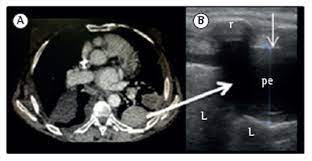

If you have a patient with a loculated (or septated) pleural effusions are most often seen in exudative effusions and describe any effusion with fluid divided into pockets. Lateral decubitus films may show loculated pleural. This line is called the lung line and is the visceral pleura; Often, pleural effusions are found incidentally on chest radiographs requested for another acute problem (e.g. Pleural effusion can be a sign of serious illness. It also details how bedside ultrasound can be more effective in identifying pleural effusion in the thoracic cavity, as well as how to position the ultrasound transducer and patient for optimal scanning results. Ultrasound signs of pleural effusions. Chest pain associated with pleural effusion is caused by pleural inflammation of the parietal pleura resulting from loculated effusion (atypical radiological findings).

And visible when both pleura are separates by a structure that allows ultrasound transmission;

Lateral decubitus films may show loculated pleural. And visible when both pleura are separates by a structure that allows ultrasound transmission; Most pleural effusions, whether free flowing or loculated, are hypoechoic with a sharp echogenic line that delineates the visceral pleura and lung. The pleura is a thin membrane that lines the surface of your lungs and the inside of your chest wall. Pleural effusions accompany a wide variety of disorders of the lung, pleura, and systemic disorders. Send aspirated fluid for cytology. Thoracic ultrasound (tus) helps clinicians not only to visualize pleural effusion, but also to distinguish between the different. When you have a pleural effusion, fluid builds up in the space between the layers of your pleura. Thoracic ultrasound has become an increasingly valuable tool in the evaluation of critically ill patients in the emergency department (ed). Ultrasound signs of pleural effusions. Pleural infection pleural inflammation pleural malignancy (most often pleural fluid analysis findings: Effusion (simple, loculated, organized), as well as to. Pleural effusion, the pathological accumulation of fluid in the pleural space, is very common.

Most pleural effusions, whether free flowing or loculated, are hypoechoic with a sharp echogenic line that delineates the visceral pleura and lung. Effusion (simple, loculated, organized), as well as to. Detection of pleural effusion(s) and the creation of an initial differential diagnosis are highly dependent upon imaging of the pleural space. Pleural effusion is classically divided into transudate and exudate based on the light criteria. Ultrasound signs of pleural effusions. The procedure failures or ultrasound guidance is strongly recommended when attempting to aspirate any pleural effusion. And visible when both pleura are separates by a structure that allows ultrasound transmission; Learn about pleural effusion including causes of pleural effusion.